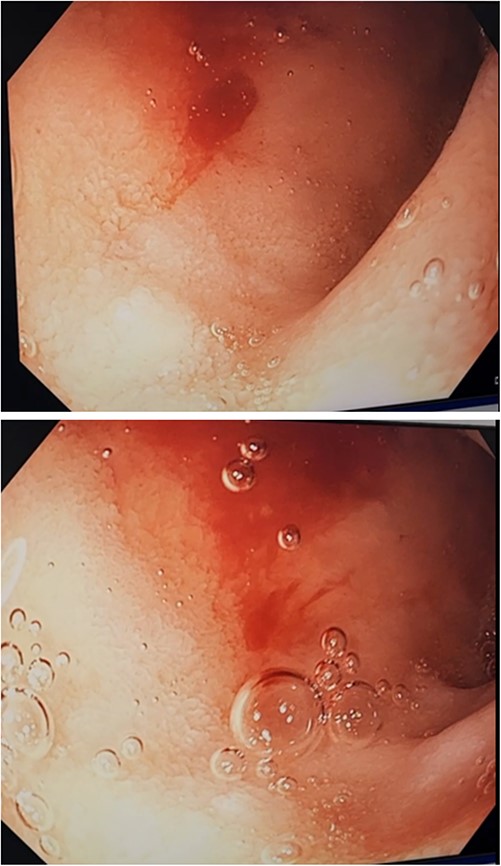

Three days after initial gastroscopy she developed further melena and anaemia, requiring additional PRBCs. She underwent a second gastroscopy, which demonstrated a lesion consistent with a DL at the junction of D1/D2 which was actively bleeding from an exposed vessel (Fig. 3). Haemostasis was achieved with thermocoagulation and adrenaline injection (Fig. 4). The melena resolved and haemoglobin remained stable. The remainder of her admission and 2-month follow-up were unremarkable.

Second gastroscopy – active arterial bleeding at D1/D2 from small mucosal defect without surrounding ulceration.